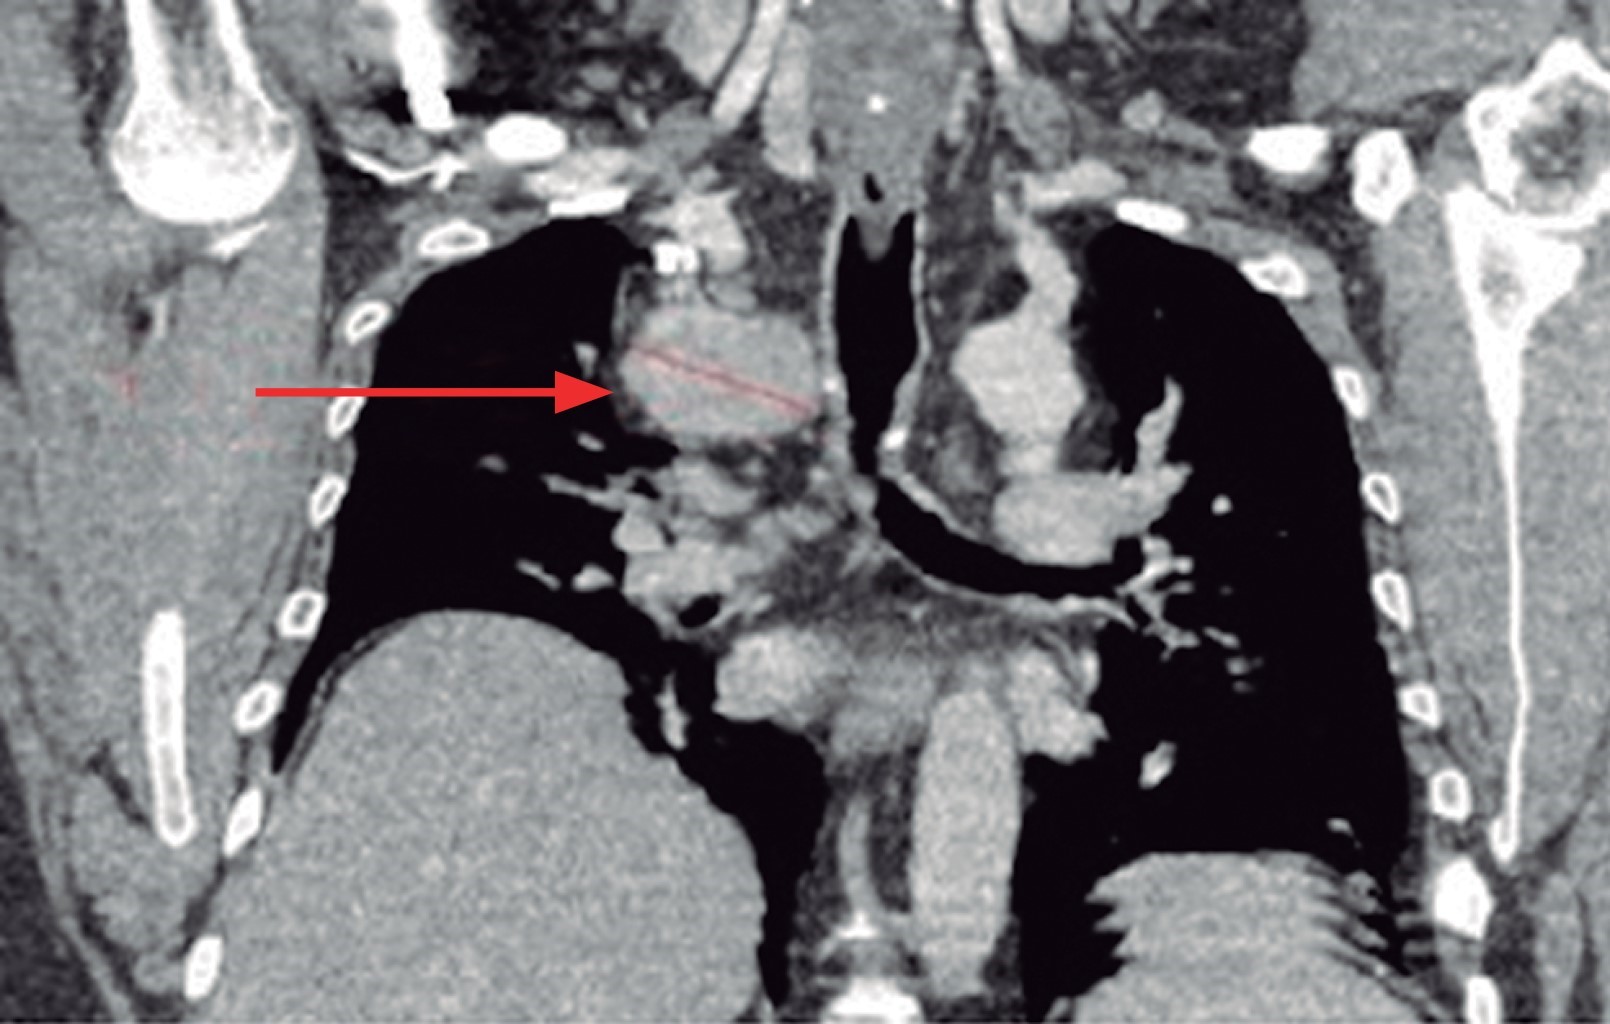

Se trata de un hombre de 47 años que había sido manejado desde hace 15 años por presentar gota, por lo que acude a consulta de reumatología, en donde refiere sintomatología respiratoria de tres meses de evolución caracterizado por tos seca en accesos, además de edema facial y extremidades superiores. Durante la revisión solicitó la radiografía rutinaria de tórax, encontrando ensanchamiento mediastínico, por lo que se realiza topografía computada, en la cual se evidencia masa en mediastino medio de aproximadamente 7 × 5 centímetros en diámetro, con compresión extrínseca de la vena cava superior y vena ácigos, elevación del hemidiafragma homolateral, además de hepatomegalia severa (Figura 1).

Figura 1